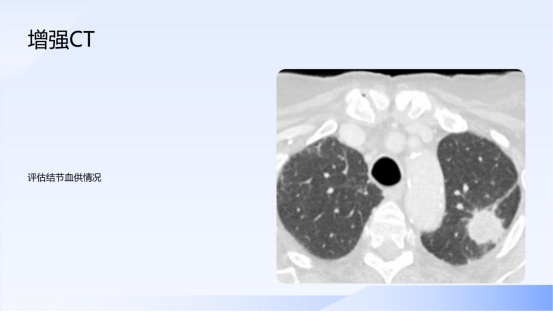

莫恐慌 重管理!肺结节科学认知十问十答